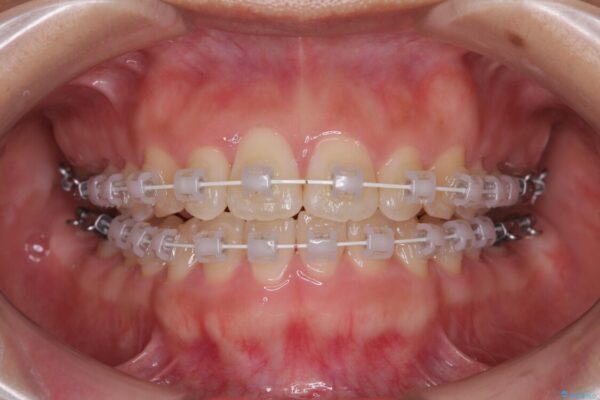

矯正装置

審美装置

・アーチを側方に拡大して歯が並ぶスペースを確保

・抜歯は避け、非抜歯での対応

・目立ちにくい審美装置による矯正

・治療期間をできるだけ短縮するために、綿密な装置管理と協力体制を構築

治療途中

• 目立ちにくい表側装置で1年完了!狭いアーチを側方拡大し前歯のデコボコを整えた症例 治療途中画像